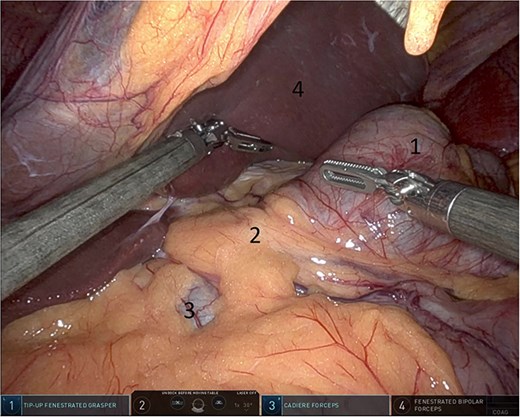

Upon entering the abdominal cavity, dilated bowel loops were observed (Fig. 2), and a significant portion of the colon was found herniated through the foramen of Winslow (Fig. 3). The herniated colon was covered by the pars flaccida (Fig. 4) (Video S1). Careful dissection was performed anterior to the hepatoduodenal ligament (Fig. 5). The gall bladder was retracted to the patient's right upper quadrant, which allowed for the retraction of the foramen of Winslow (Fig. 6) (Video S1). After carefully placing the tip of the instrument posterior to the portal vein and gently elevating it, the herniated colon was successfully reduced (Fig. 7) (Video S1).

Herniated colon through the foramen of Winslow (1: incarcerated colon, 2: hepato-duodenal ligament, 3: herniating colon, 4: the liver).